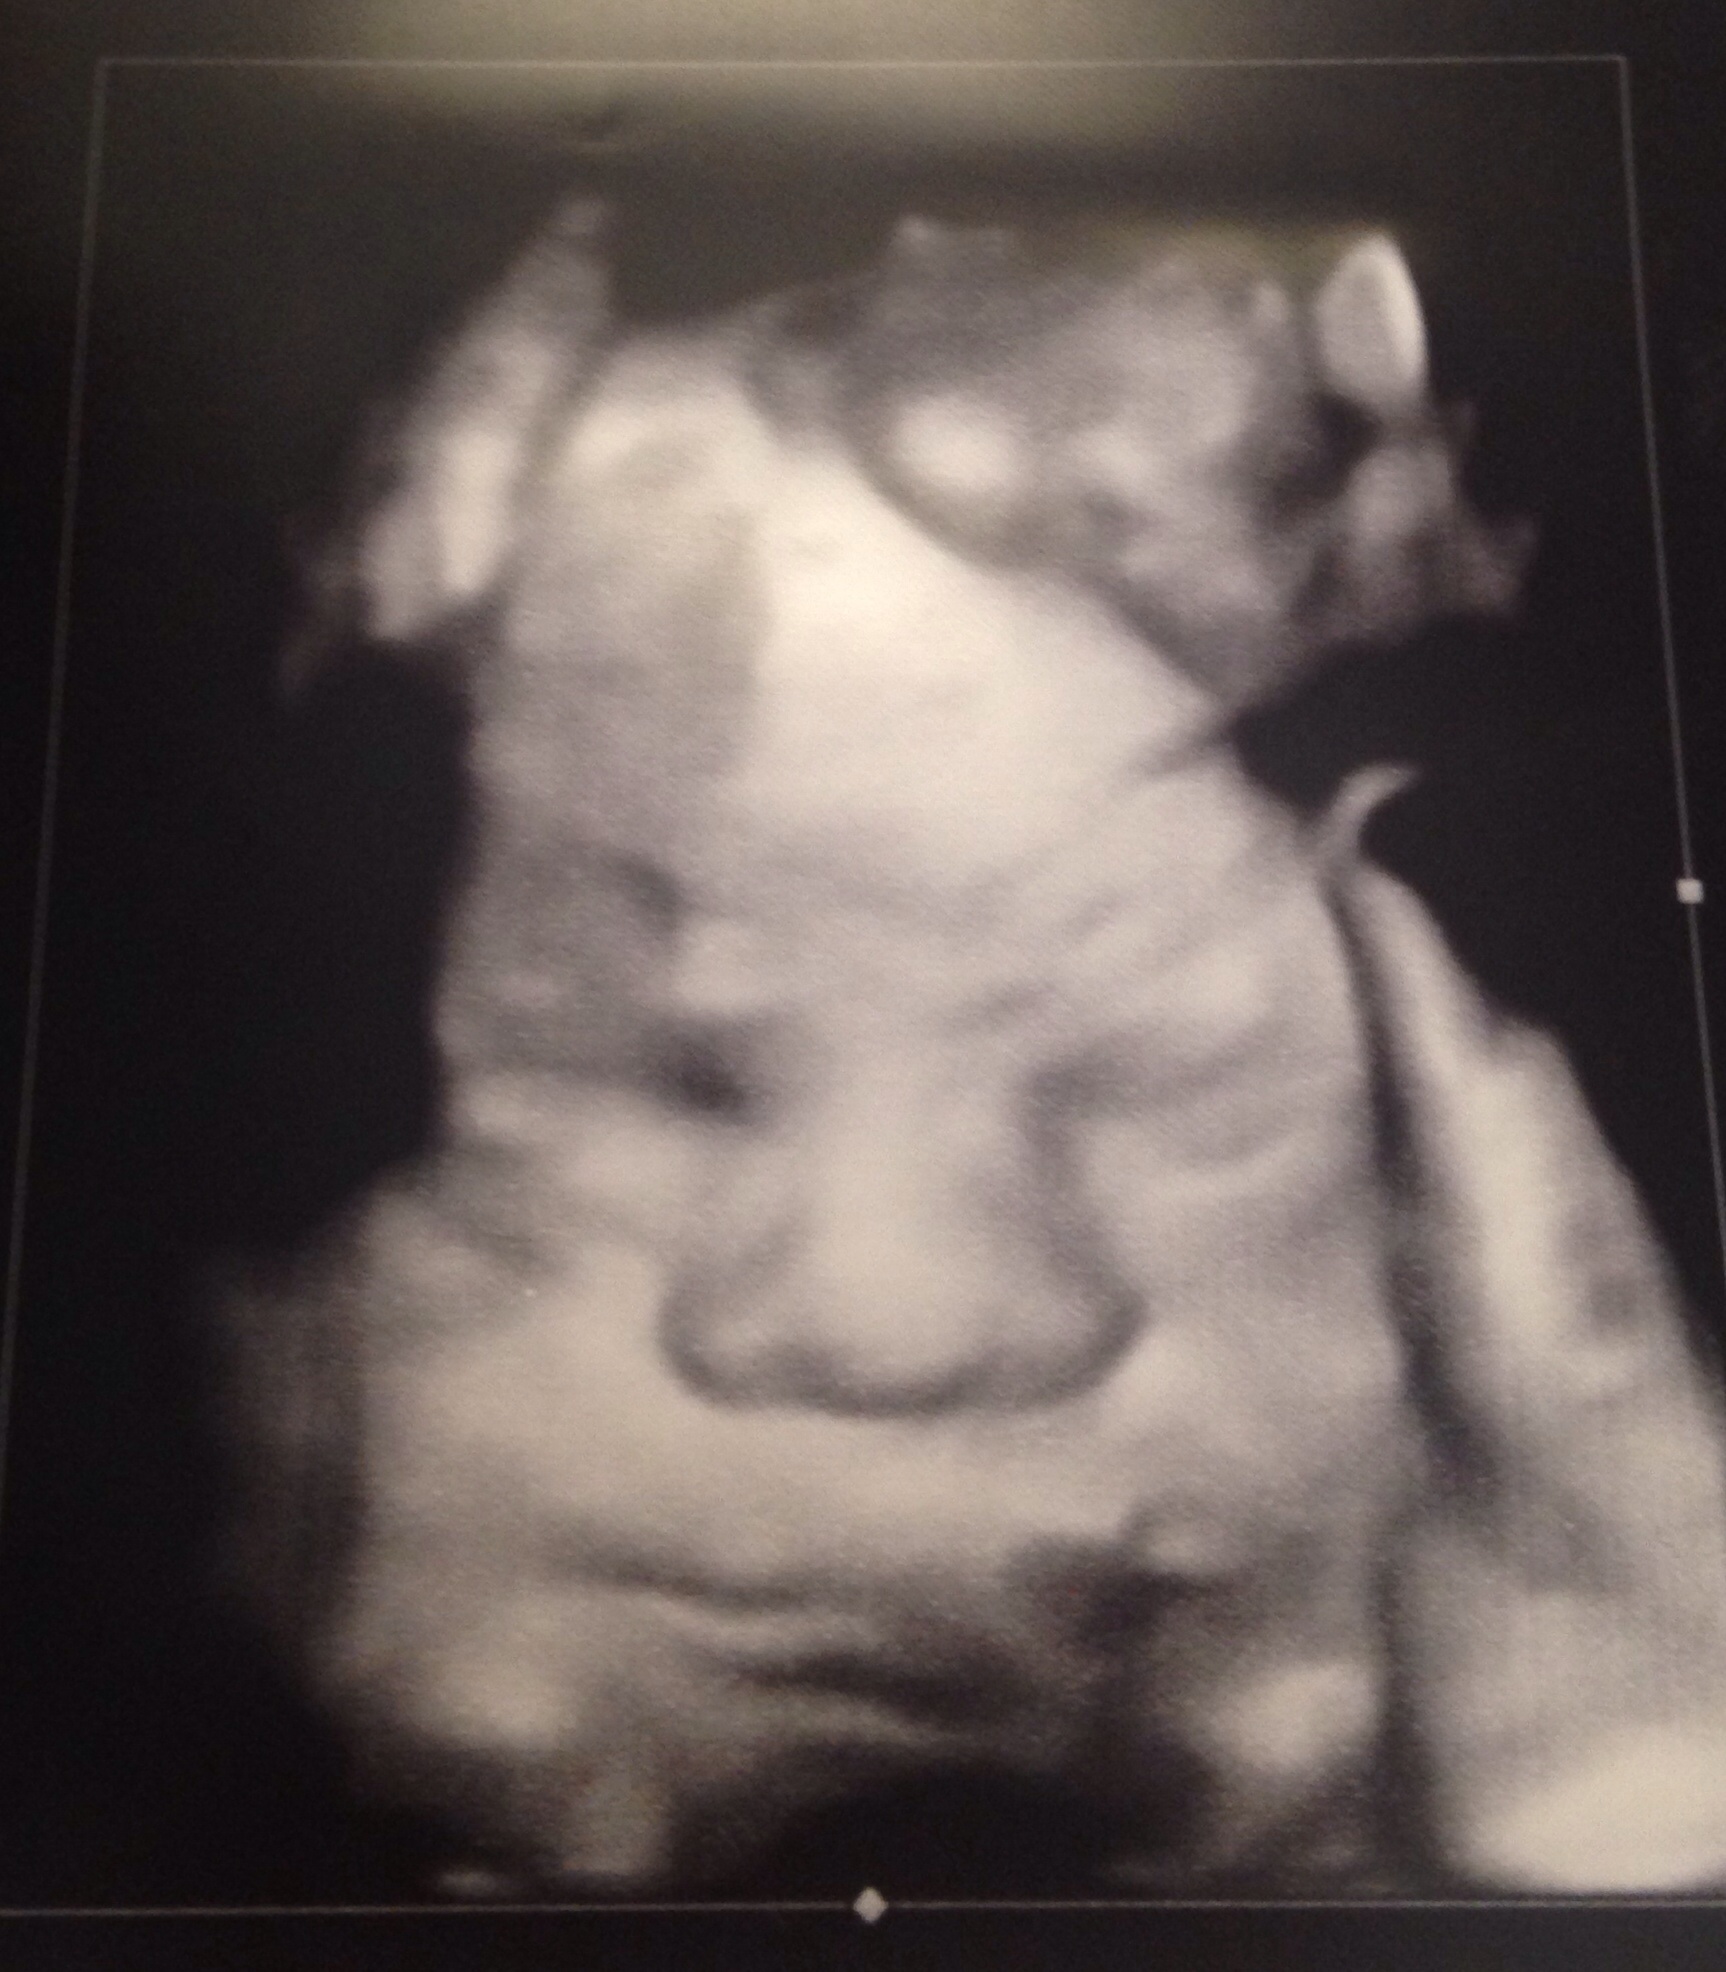

Baby is 27w5d and measuring 2lbs, which I'm told is slightly above average but still ok. So exciting every time I see our little nugget! :x

TTC since 11/2011 Me: Hypothyroid & PCOS DH: 0% morphology IVF #1 - transfer on 4/2/14 BFP 4/11/14 beta 161 EDD: 12/19/14 It's a GIRL! AnaSophia (Sophie; Soph the Loaf)